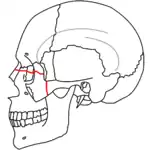

At the beginning of the 20th century, René Le Fort mapped typical locations for facial fractures; these are now known as Le Fort I, II, and III fractures (right).[7] Le Fort I fractures, also called Guérin or horizontal maxillary fractures,[14] involve the maxilla, separating it from the palate.[15] Le Fort II fractures, also called pyramidal fractures of the maxilla,[16] cross the nasal bones and the orbital rim.[15] Le Fort III fractures, also called craniofacial disjunction and transverse facial fractures,[17] cross the front of the maxilla and involve the lacrimal bone, the lamina papyracea, and the orbital floor, and often involve the ethmoid bone,[15] are the most serious.[18] Le Fort fractures, which account for 10–20% of facial fractures, are often associated with other serious injuries.[15] Le Fort made his classifications based on work with cadaver skulls, and the classification system has been criticized as imprecise and simplistic since most midface fractures involve a combination of Le Fort fractures.[15] Although most facial fractures do not follow the patterns described by Le Fort precisely, the system is still used to categorize injuries.[5]